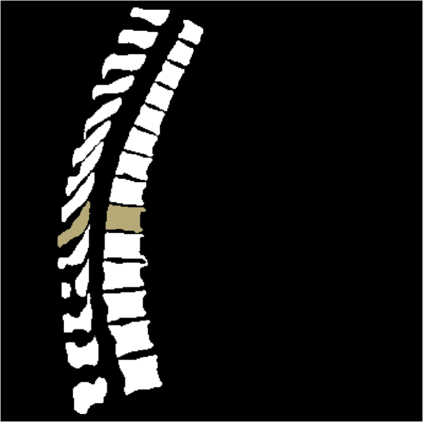

Vertebrae localization, segmentation and identification in CT images is key to numerous clinical applications. While deep learning strategies have brought to this field significant improvements over recent years, transitional and pathological vertebrae are still plaguing most existing approaches as a consequence of their poor representation in training datasets. Alternatively, proposed non-learning based methods take benefit of prior knowledge to handle such particular cases. In this work we propose to combine both strategies. To this purpose we introduce an iterative cycle in which individual vertebrae are recursively localized, segmented and identified using deep-networks, while anatomic consistency is enforced using statistical priors. In this strategy, the transitional vertebrae identification is handled by encoding their configurations in a graphical model that aggregates local deep-network predictions into an anatomically consistent final result. Our approach achieves state-of-the-art results on the VerSe20 challenge benchmark, and outperforms all methods on transitional vertebrae as well as the generalization to the VerSe19 challenge benchmark. Furthermore, our method can detect and report inconsistent spine regions that do not satisfy the anatomic consistency priors. Our code and model are openly available for research purposes.